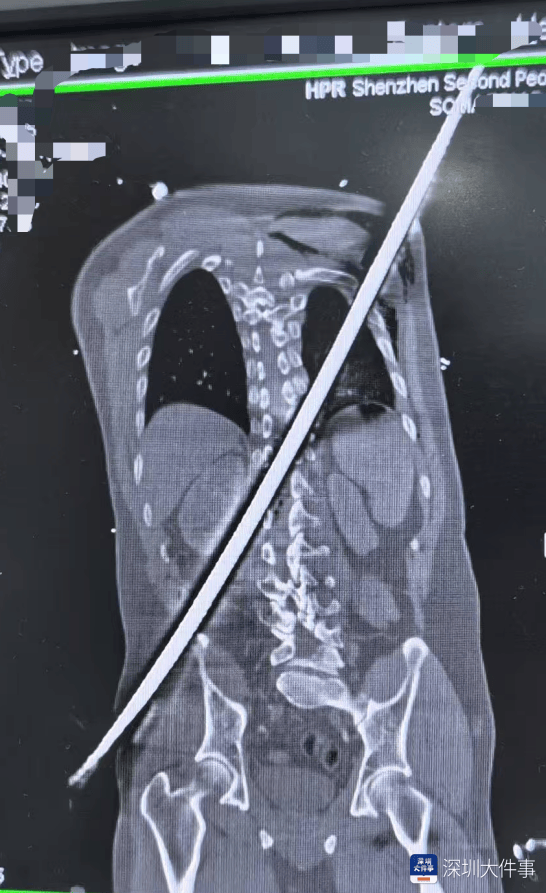

一根67厘米(mi)长的(de)粗(cu)壮钢筋,从右(you)边臀部斜穿至左(zuo)后侧肩背,将一名男子(zi)生命(ming)推向悬崖(ya)边沿(yan)!近(jin)日,深圳市第二人民(min)医院(下称“深圳二院”)启动(dong)紧急(ji)救援机制,多学科专家精准协(xie)作,历(li)经手术攻坚与术后抗熏染守(shou)护,成功从死神手中夺回该名男性(xing)伤(shang)者生命(ming)。

日前,一名男子(zi)被一根67厘米(mi)长的(de)钢筋从右(you)边臀部刺(ci)入,斜穿身体后从左(zuo)后侧肩背贯穿而(er)出。送医时,男子(zi)已(yi)出现失血性(xing)休克,双下肢无法活(huo)动(dong)。深圳二院脊柱外科周文钰主任引见,患者送医时已(yi)陷入休克状态(tai),生命(ming)体征微弱。“患者病情危急(ji),钢筋贯穿路(lu)径复杂,稍(shao)有不慎便会引发致命(ming)大出血,必须立即启动(dong)应(ying)急(ji)救治流程(cheng)。”

满身CT扫描精准勾勒出钢筋在体内(nei)的(de)“行走路(lu)径”:钢筋险之又险地穿过腹膜(mo)后间隙,击穿胸腰段脊柱椎管,最终穿入胸腔,其路(lu)径紧贴肾脏、大血管等枢纽(niu)脏器(qi)——每次心跳,都(dou)大概让(rang)钢筋锋刃与血管产生摩擦,引发劫难性(xing)大出血。